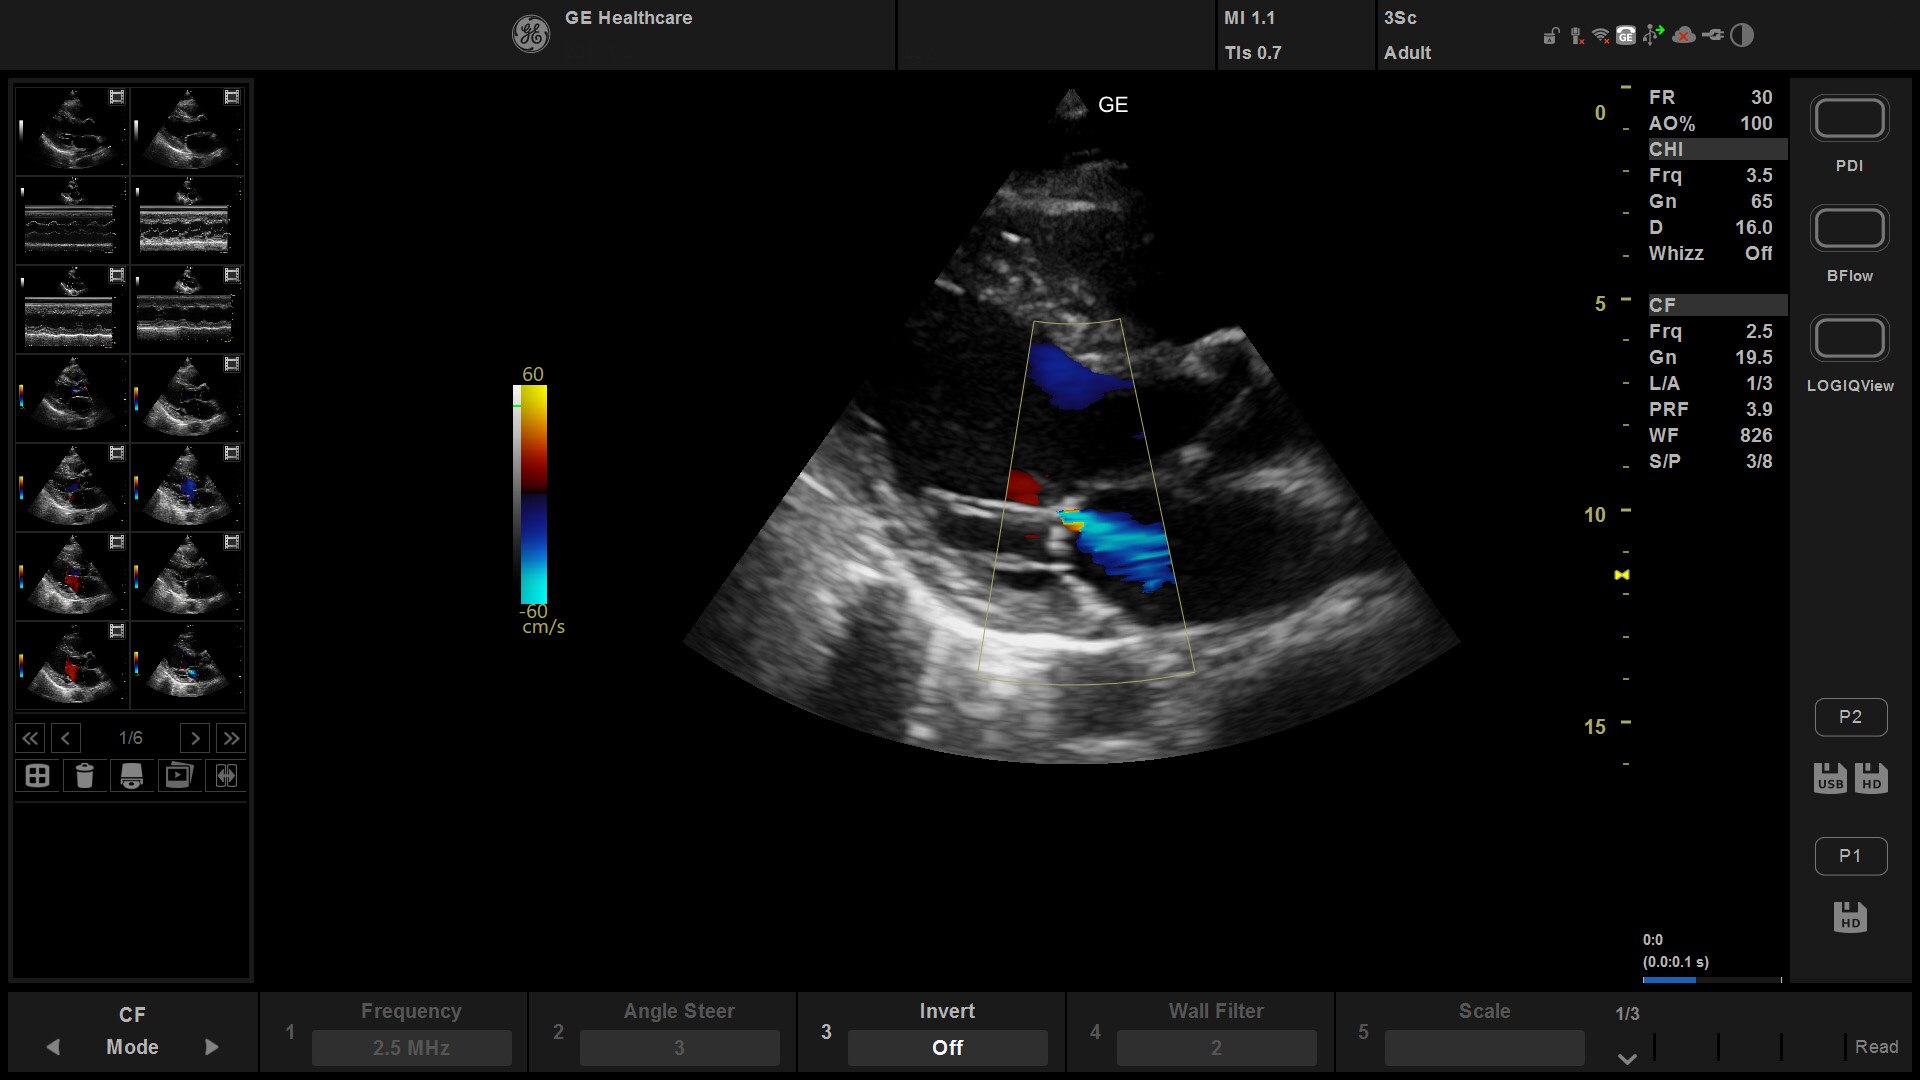

Offering anesthesiologists an effortless, multi-purpose ultrasound system, the Venue™ family helps  confidently decrease the risk of complications during nerve block procedures. Vibrant images and a powerful suite of tools allow you to see nerves and surrounding anatomy quickly and clearly to optimize local anesthetic distribution.

Helping improve patient outcomes by reducing error rates, Venue’s imaging software is optimized to help the nerve stand out from other types of tissue. Allowing you to differentiate between the needle and patient anatomy with confidence, Venue family systems guide you with a real-time view of anatomy, needle advancement and local anesthetic spread.